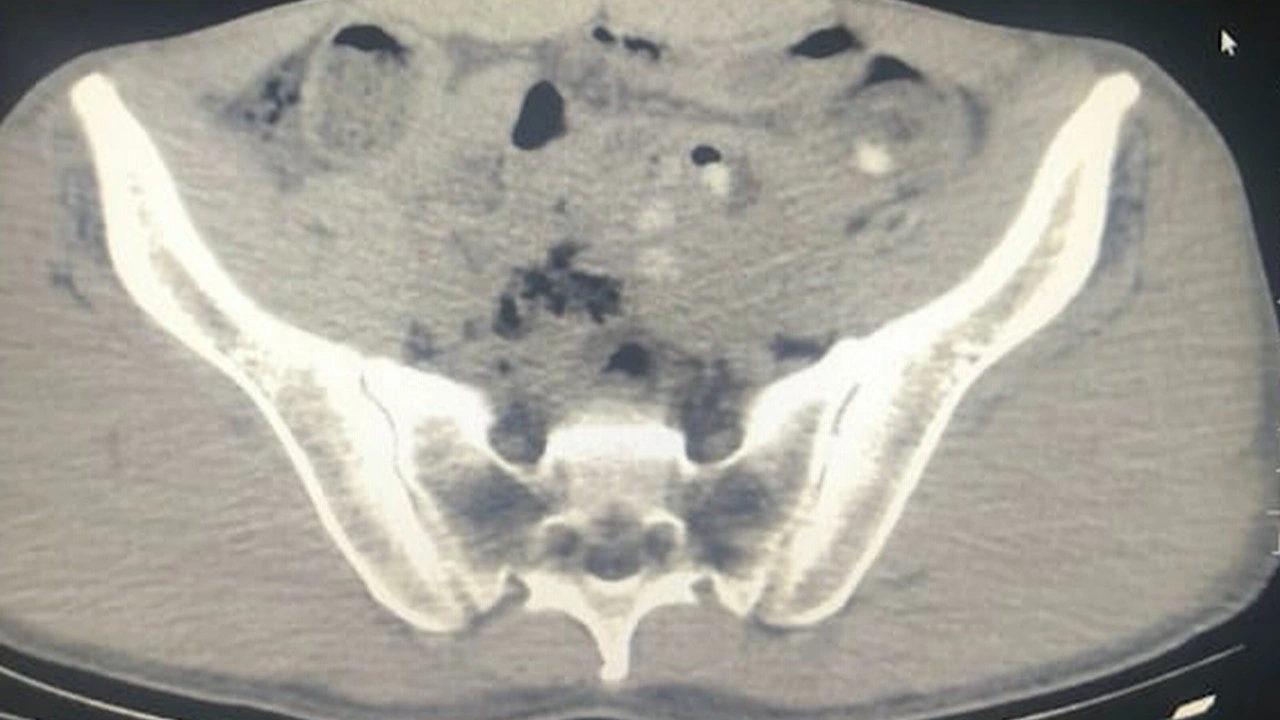

Gözaltına alınıp hastaneye götürülün şüphelilerin çekilen röntgenlerinde de midelerinde 45 kapsül metamfetamin tespit edildi.

Şüphelilerin midesindeki uyuşturucu doğal yollarla çıkarıldı.